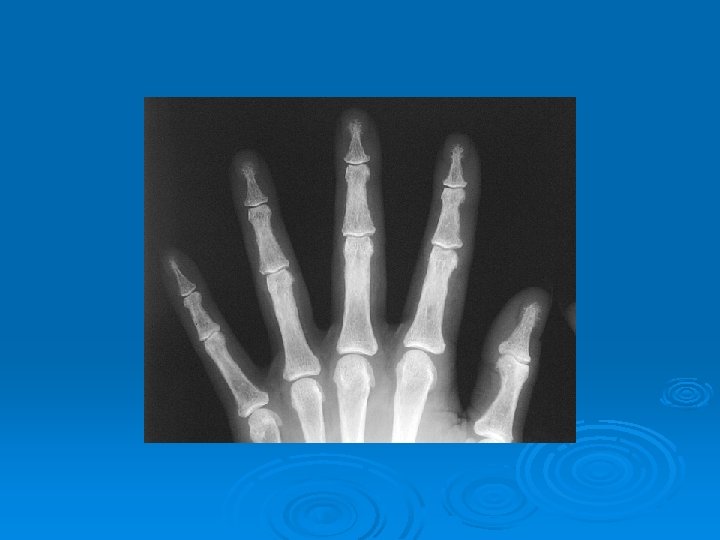

Imaging Studies Ø Ultrasonography and 99 m. Tc sestamibi scanning have the advantages of being widely available and relatively inexpensive compared but is operator-dependent. Ø Radiology ---- subperiosteal resorption at the radial sides of the phalanges, distal phalangeal tufts, and distal clavicles. Ø Skull Xray ---- pepar salt apperance . Ø (DXA) at the hip and spine ---- ostoprosis.